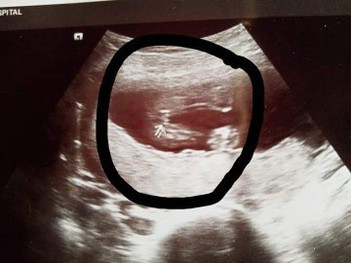

คุณแม่ว่าผู้หญิงหรือชายค่ะซาวตอน18วิค